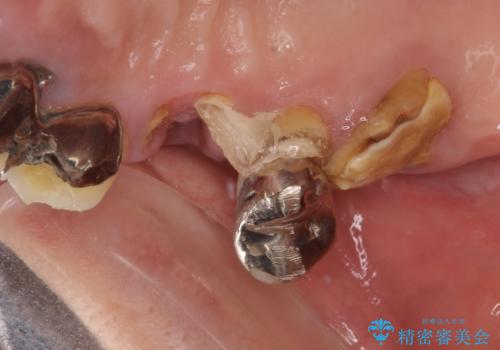

臼歯はもはや咬み合わせに寄与していない状態であり、3歯を抜去してインプラント2本埋入によるブリッジ補綴を計画しました。

臼歯部は前歯以上に炎症が酷く、抜歯即時埋入不可と判断されましたが、従来法よりは短期間で終えることができました。